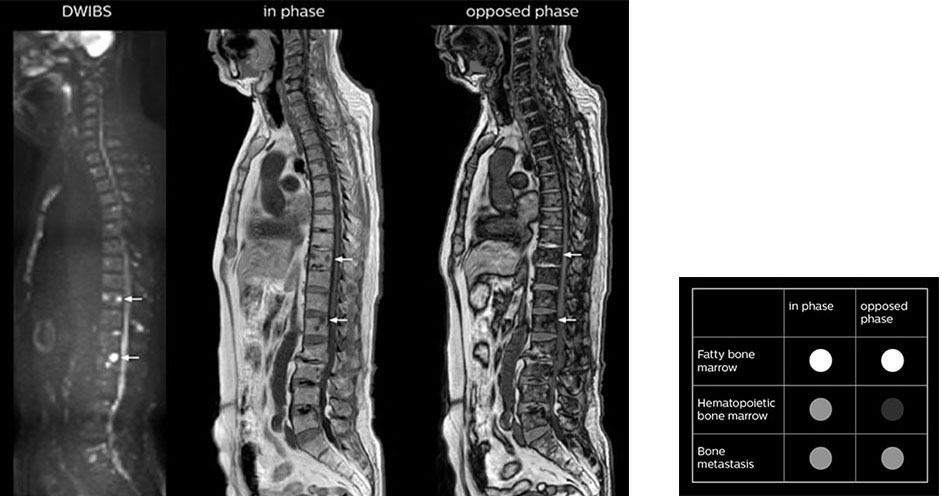

The single shot T2-weighted TSE images are used for morphology and compared to DWIBS images to identify T2 shine-through. Sagittal STIR images are used in patients with inflammation or bone metastasis.

“mDIXON FFE allows us to quickly get information we need to assess the presence of fat. That gives us more information when we need to diagnose bone lesions, and when we are asked to judge fat-containing lesions such as hepatocellular or renal carcinoma,” Dr. Nobusawa says.

“The mDIXON fat images can help us to differentiate fatty bone marrow from bone lesions. This is especially useful in elderly people, who tend to have fattier bone marrow. The water images provide a high signal-to-noise ratio in the intestinal canal, which is valuable for visualizing lesions in the colon,” he says.

“In-phase and out-phase sagittal T1-weighted FFE images help us to visualize and further characterize bone lesions such as metastasis and bone-marrow hyperplasia that have high signal on DWI. These images are also used throughout radiotherapy, to monitor changes in the fatty bone marrow.”